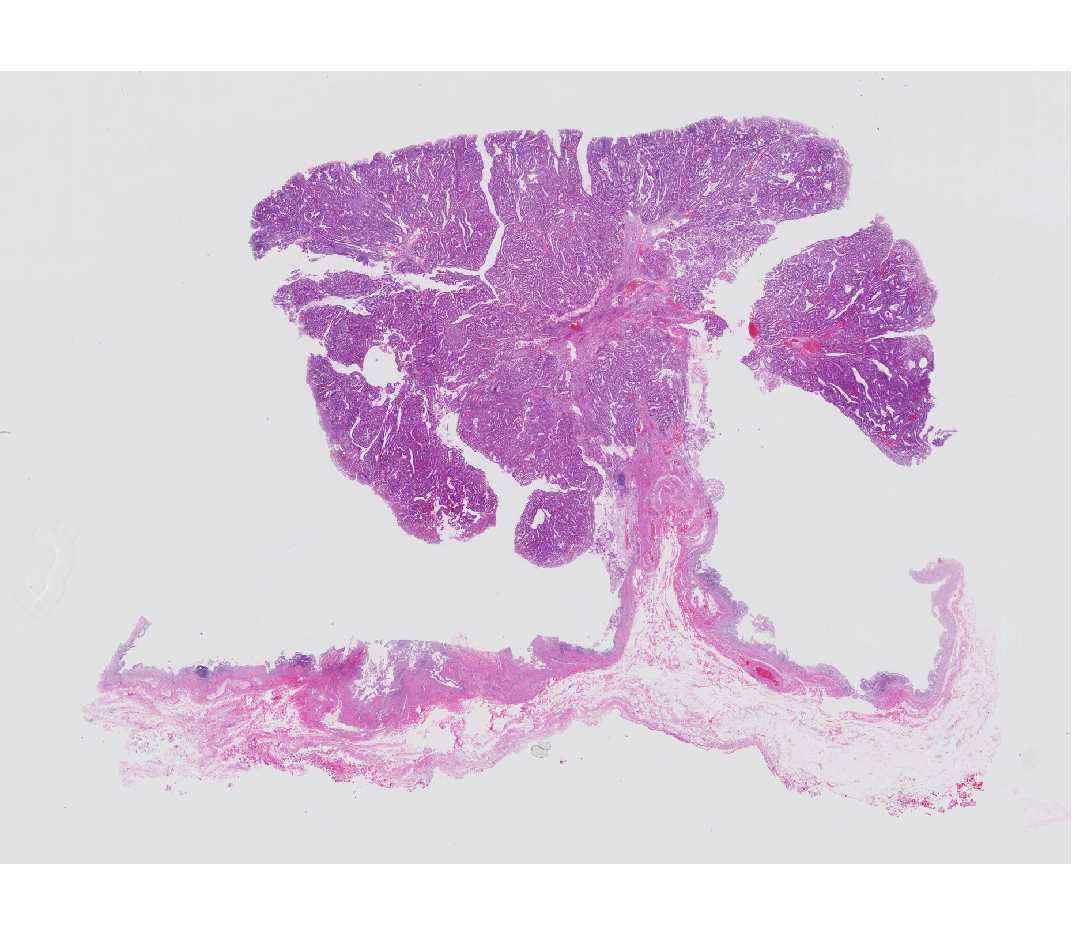

Cell tree

꼭  분재 나무처럼 생겼습니다.

현미경 촬영용 디지탈 카메라가 따로 있습니다, 현미경 상단에 붙여서 사용하기 때문에 일반 디카로는 이런 사진을 찍을 수는 없습니다.

현미경과 디카만 있어도 안되고 컴퓨터 여러가지 부속품들이 필요하죠, 아래 사진과 같다고 보시면 됩니다.